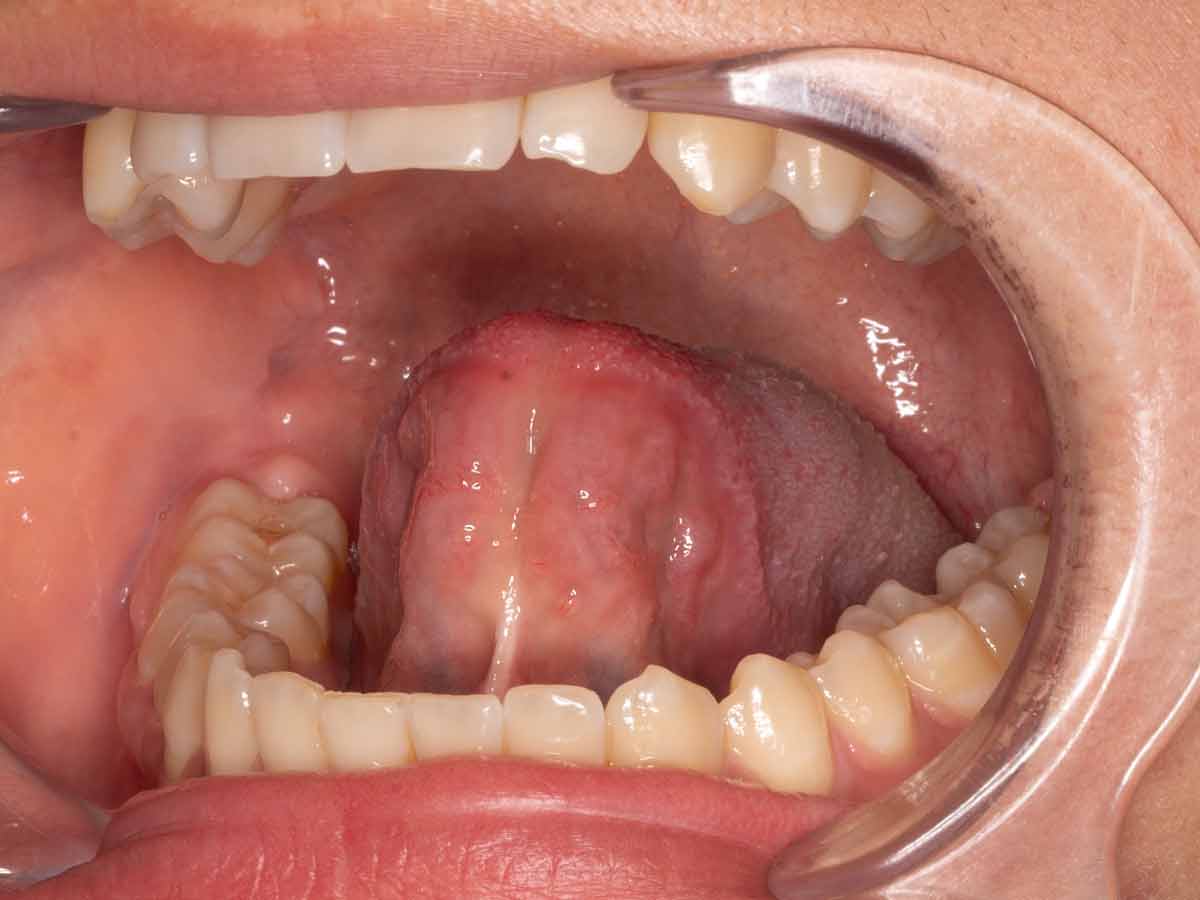

Resección de frenillo lingual con electrocirugía | Clínica Manhood Puerto Varas

Caso clínico de resección de frenillo lingual en paciente de 13 años, tratado con electrocirugía sin sutura, mínima hemorragia y liberación funcional inmediata de la lengua en Clínica Manhood Puerto Varas.